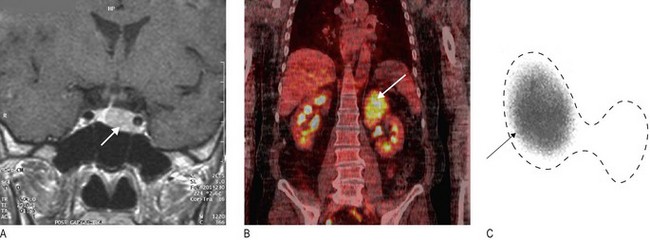

Fig. 5.22 Endocrine imaging.

(A) Magnetic resonance imaging showing pituitary macroadenoma (arrow). (B) Positron emission tomography-computed tomography scan showing an adrenal cancer (arrow). (C) 99mTechnetium radionuclide scan confirming unilateral toxic thyroid adenoma (arrowed) – dotted line shows outline of thyroid.